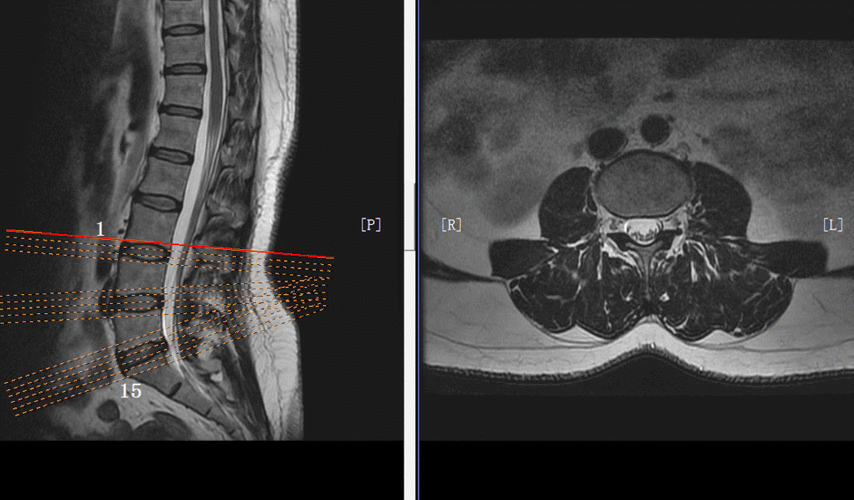

图示:矢壮位mri显示的颈椎结构和区域.白点:为上位椎屈伸运动中心.